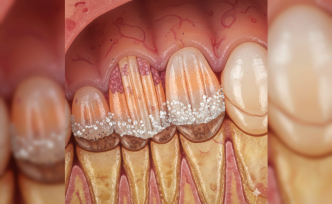

Nadir Görülen Axenfeld-Rieger Sendromu Hakkında Uzman Uyarısı

Tıp dünyasında nadir rastlanan genetik bozukluklar arasında yer alan Axenfeld-Rieger sendromu, özellikle göz yapısı ve diş gelişimi üzerindeki etkileriyle dikkat çekiyor. Doğuştan gelen bu durum, her 200 bin doğumda bir görülmesine rağmen erken teşhis edilmediğinde ciddi görme kayıplarına yol açabiliyor. Uzmanlar ailelerin bebeklik dönemindeki rutin kontrolleri aksatmaması gerektiğini belirtiyor.